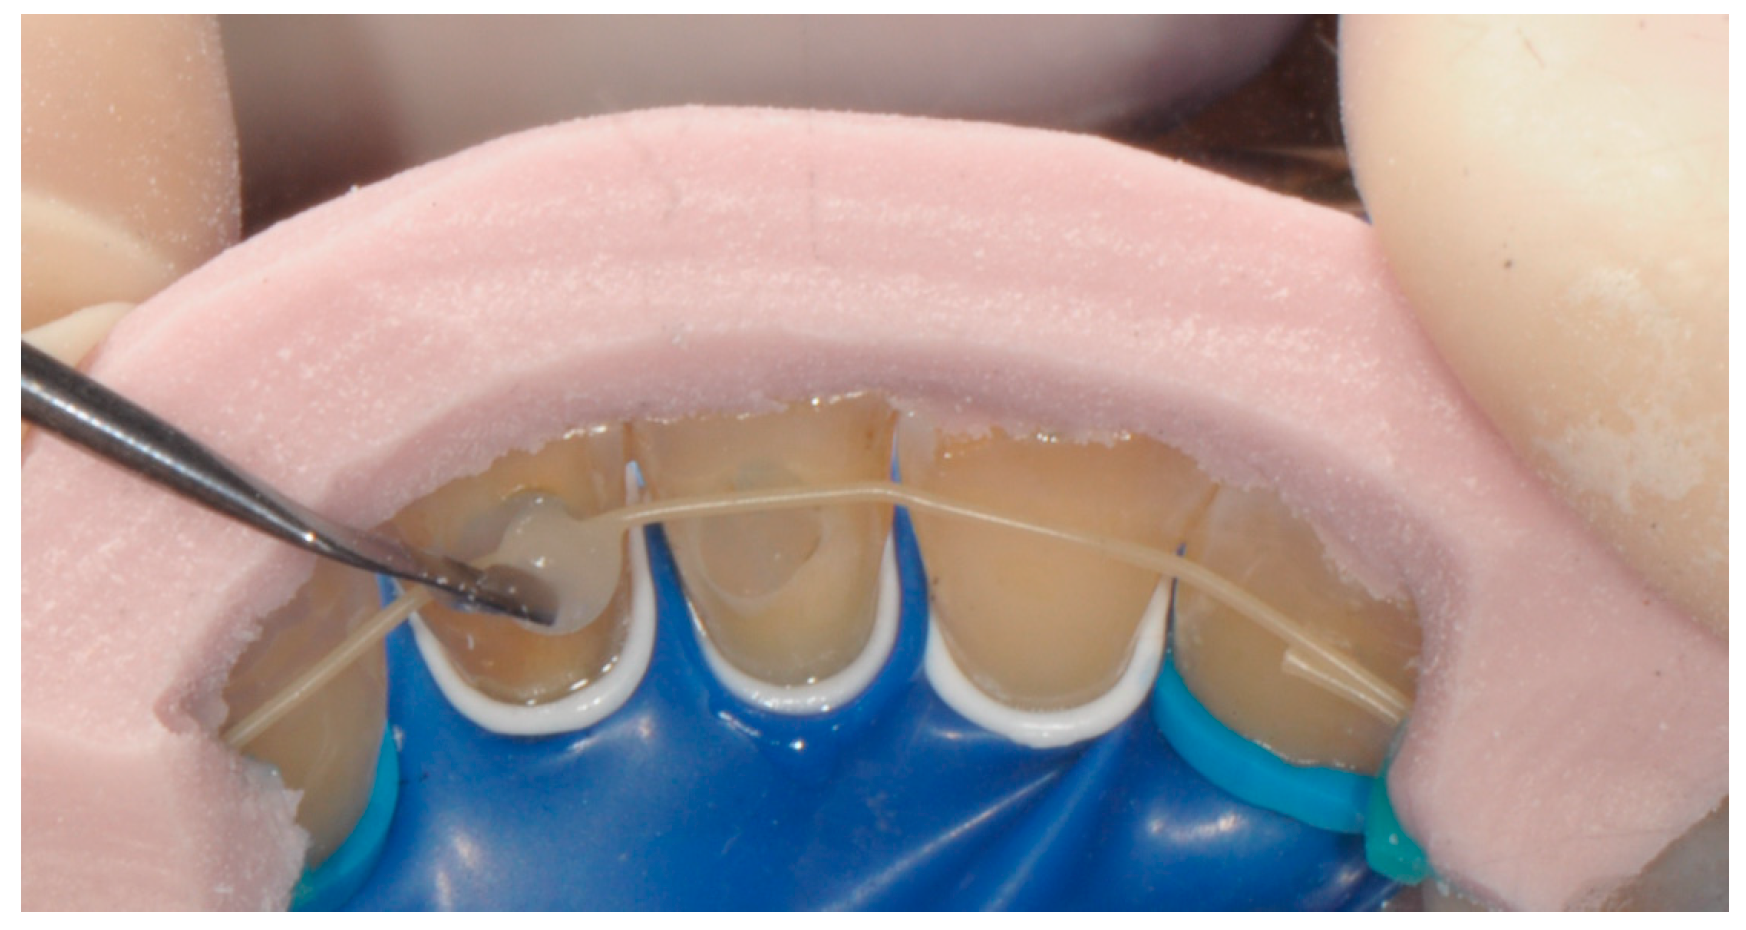

2. Materials and Methods